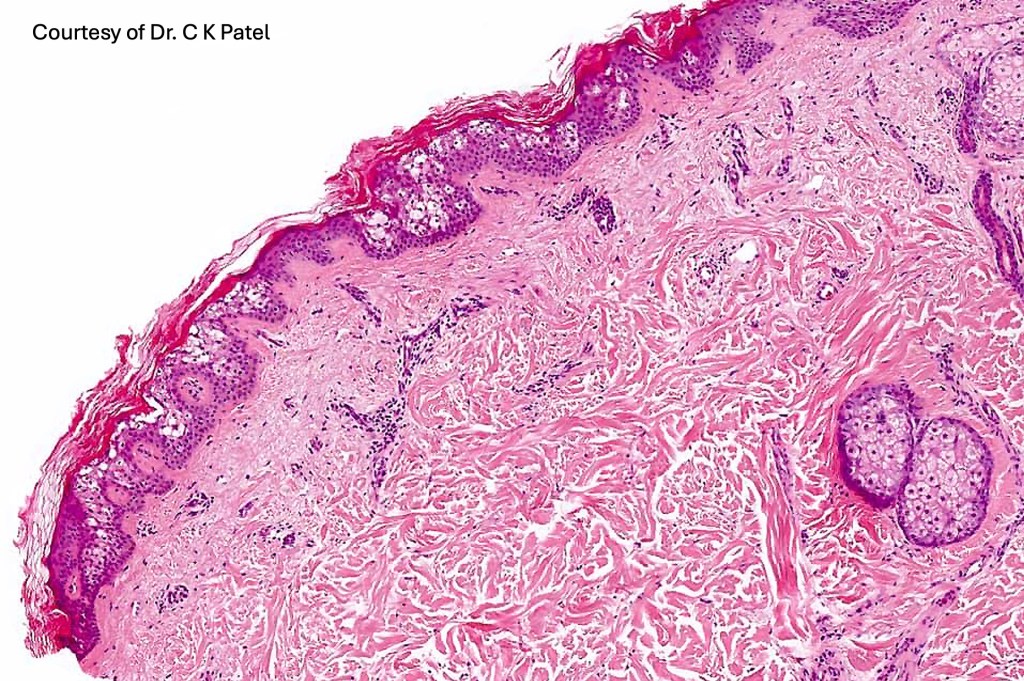

•Cup-shaped circumscribed lesion showing hyperkeratosis, focal parakeratosis & acanthosis

•Superficial epidermis shows often multifocal keratinocyte vacuolation with eosinophilic cytoplasmic inclusions & sometimes epidermal necrosis

•Incidental epidermolytic hyperkeratosis presents as a very small focus of histologically change in specimens from a wide range of unrelated conditions such as nevi, seborrheic keratoses, actinic keratoses etc and normal skin